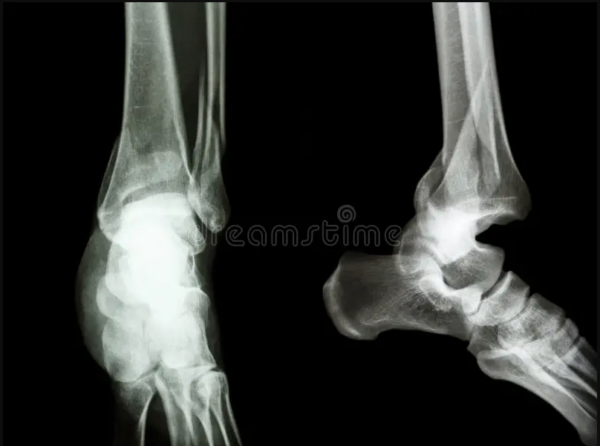

Las fracturas por sobrecarga pueden afectar a cualquiera que haga deporte. “Afectan por igual a los profesionales como a los aficionados. Se trata de una sobrecarga relativa”, explica a DW Español Karsten Hollander. Hollander es profesor de medicina deportiva en la facultad de medicina de Hamburgo y médico jefe de la Asociación Alemana de Atletismo (DLV). Una fractura clásica se produce cuando se ejerce una fuerza repentina sobre un hueso, sea por un golpe o una patada, por ejemplo. Por otro lado, una fractura por fatiga es el resultado de un proceso gradual. PROCESO ACUMULATIVO “El dolor suele presentarse al principio de la carrera y empeora hasta impedir seguirla”, explica Hollande, corredor de media distancia. “Esto es diferente de las lesiones tendinosas porque estas pueden no ser tan dolorosas después de la fase de calentamiento como lo eran al principio”. Las principales zonas de riesgo al correr son la tibia y el pie. Si experimenta dolor tirante en esas zonas, debe consultar a un médico. Los procedimientos de diagnóstico por imagen, como la resonancia magnética o la gammagrafía, proporcionarán entonces la certeza definitiva sobre si ha sufrido una fractura por fatiga. La fractura por estrés puede darse, en principio, en cualquier tipo de deporte. Los huesos que corren mayor riesgo son los que están sometidos a un esfuerzo especial. MUJERES, CON MÁS RIESGOS Sin embargo, la mayoría de las fracturas por estrés se registran en la práctica del atletismo. “En Alemania, el ‘running’ es una práctica deportiva muy popular, esto da lugar a un elevado número de casos”, explica Hollander, médico de la asociación DLV. Las mujeres tienen casi el doble de probabilidades de sufrir una fractura por estrés que los hombres. y, en segundo lugar, debido a niveles hormonales. “Los estrógenos [hormonas sexuales femeninas] son importantes para el metabolismo óseo”, explica el médico deportivo Hollander. “El tipo de anticonceptivo también puede influir: ¿Hasta qué punto interfieren los preparados en el metabolismo?”. Por este motivo, los ginecólogos deportivos también forman parte ahora de la red médica de la DLV. DOBLE DE POSIBILIDADES Según los estudios, las mujeres tienen aproximadamente el doble de probabilidades de sufrir una fractura por estrés que los hombres. Esto se debe a varias razones. En primer lugar, las mujeres suelen tener una menor densidad ósea y, en segundo lugar, los niveles hormonales. A todo esto, hay que agregar que los trastornos alimentarios son más frecuentes entre las deportistas y esto aumenta el riesgo de fracturas por estrés. CALCIO NECESARIO Para prevenir este tipo de fracturas, los deportistas deben asegurarse de que su organismo recibe un aporte suficiente de calcio y vitamina D. El calcio estabiliza los huesos, mientras que la vitamina D garantiza una mejor absorción del calcio por el organismo y su incorporación a los huesos. “Los vegetarianos y veganos que utilizan sustitutos de la leche deben tener cuidado. Los hay con calcio y sin calcio”, señala Hollander. Aunque, también puede ser peligroso tomar demasiado calcio ya que puede aumentar el riesgo de cálculos renales”. FRACTURAS FRECUENTES Dado que las fracturas por estrés son el resultado de la sobrecarga de los huesos, Hollander recomienda una gestión adecuada del entrenamiento. “No se debe aumentar la carga de trabajo en más de un 20% de una semana a otra. Esto se aplica a la distancia total recorrida por semana, la longitud de la carrera más larga, pero también a la intensidad y el alcance de los intervalos individuales de carrera”. Las aplicaciones de fitness pueden ayudar a controlar el esfuerzo con ayuda del celular. Un análisis biomecánico es recomendable. ¿Y si se produce una fractura por fatiga? Entonces la máxima prioridad es proteger el hueso afectado. A diferencia de las fracturas “clásicas”, en las fracturas por sobrecarga las partes rotas del hueso rara vez se desplazan. Por tanto, no suele ser necesario inmovilizar el hueso con una placa. (Fotos: Tomada de DW Español) Compartir Navegación de entradas Crean dispositivo para leer emociones humanas en tiempo real Experimentan con orina humana como alternativa para crear fertilizante